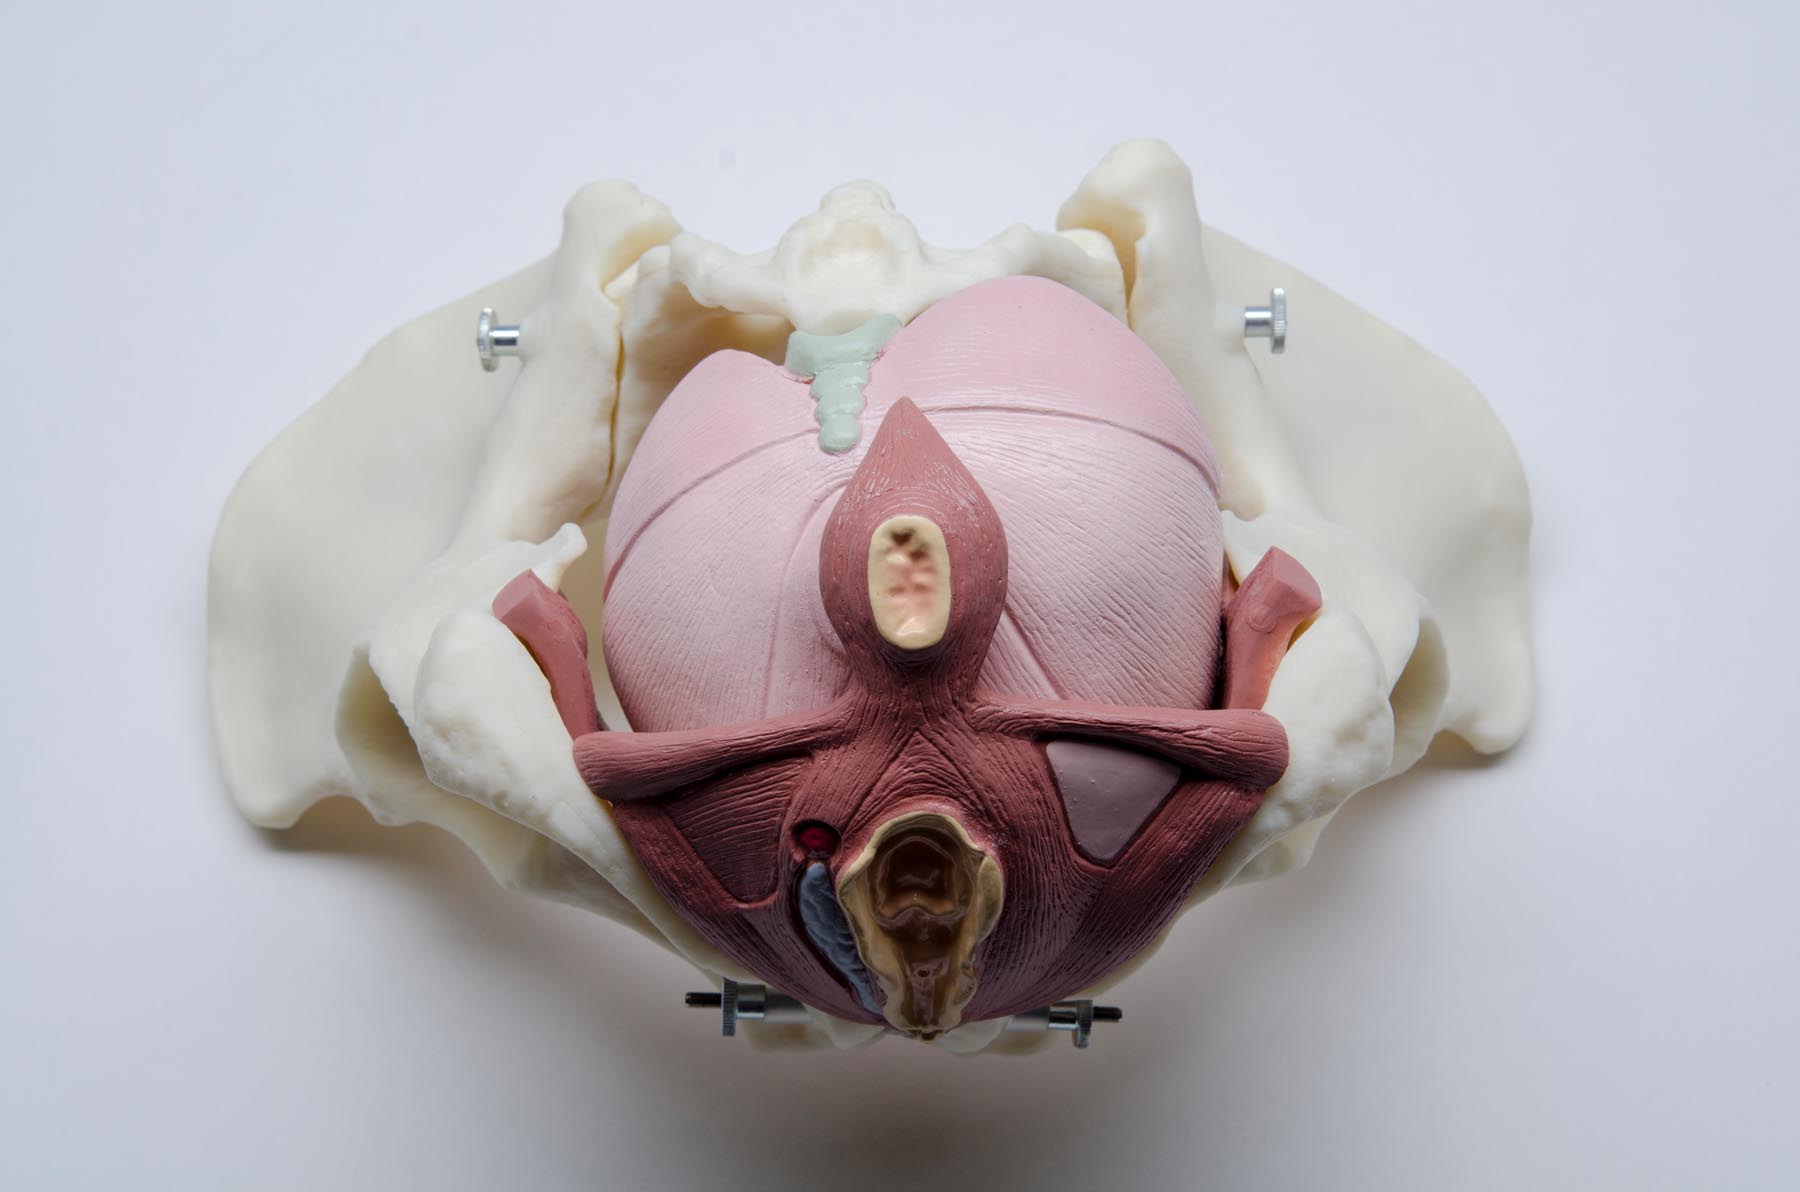

A complete life-size female pelvis with a highly detailed pelvic floor made of flexible plastic. Features the genitalia and associated muscles. Dissects into 5 parts.